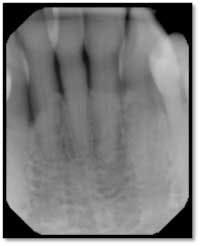

A full set of radiographs taken 13 months post therapy show bone fill in the deepest pockets, with generalized pocket reductions of up to 7mm.

#3 was referred for endodontic evaluation.

#’s 15 and 18 show no signs of endodontic involvement, #15 tests vital.

This patient now has a periodontally stable dentition for the first time in his adult life and is very happy with the outcome of his therapy.